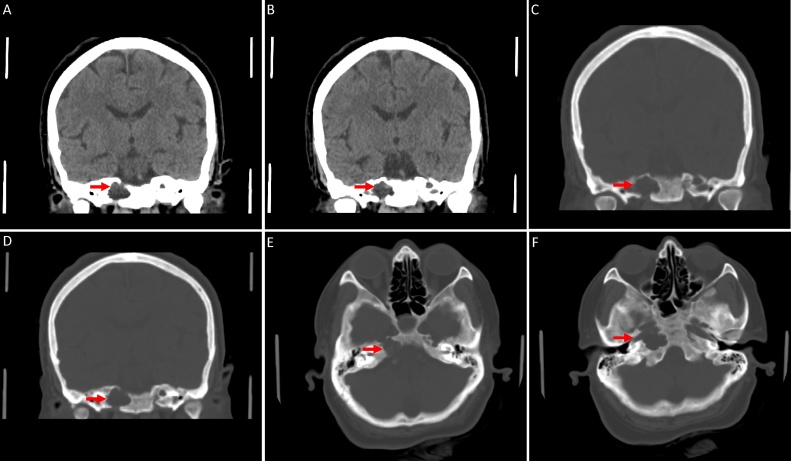

Neuroimaging studies were performed to investigate the possible causes of her headache. The brain MRI showed CSF-containing lesions with no enhancement in the petrous apices bilaterally, communicating with Meckel’s cave (Fig. 1). The non-enhanced CT scan of the brain revealed bilateral osteolytic bony lesions in the petrous apices with fluid density (Fig. 2).

Fig. 2.

Nonenhanced CT brain; (A-B) Coronal brain window. (C-F) Coronal and axial bone window. (A-F) There are bilateral, well-defined, lytic, expansile, fluid-containing lesions in the petrous apices with bone dehiscence of the inner cortex of the petrous bone.